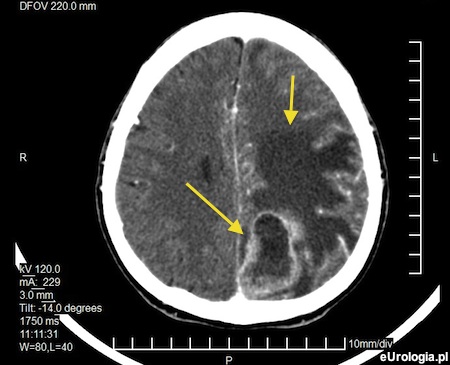

Fot. Skan tomografii komputerowej u wykonanej u pacjenta z przerzutowym rakiem gruczołu krokowego. Strzałkami zaznaczono ogniska metastatyczne.